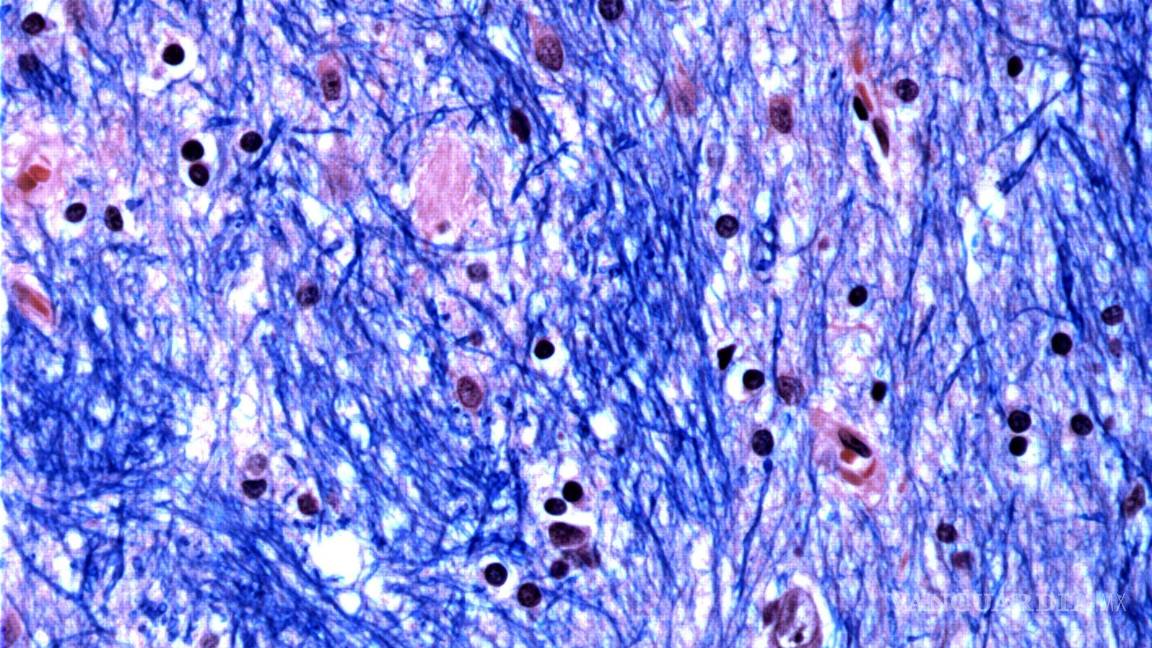

La muerte de las células cerebrales eventualmente conduce a problemas con el movimiento, el pensamiento y el comportamiento. Los síntomas de Huntington, que incluyen movimiento involuntario, marcha inestable, cambios de personalidad y juicio deteriorado, comienzan típicamente entre los 30 y 50 años, empeorando gradualmente durante 10 a 25 años.

Se centraron en la mutación de Huntington, que involucra un tramo de ADN en un gen particular donde una secuencia de tres letras, CAG, se repite al menos 40 veces. En personas sin la enfermedad, esta secuencia se repite sólo de 15 a 35 veces. Descubrieron que los tramos de ADN con 40 o más “repeticiones” se expanden con el tiempo hasta que tienen cientos de CAGs. Una vez que los CAGs alcanzan un umbral de aproximadamente 150, ciertos tipos de neuronas enferman y mueren.

El equipo de investigación estimó que los tramos de repetición crecen lentamente durante las primeras dos décadas de vida, luego la tasa se acelera dramáticamente cuando alcanzan alrededor de 80 CAGs.